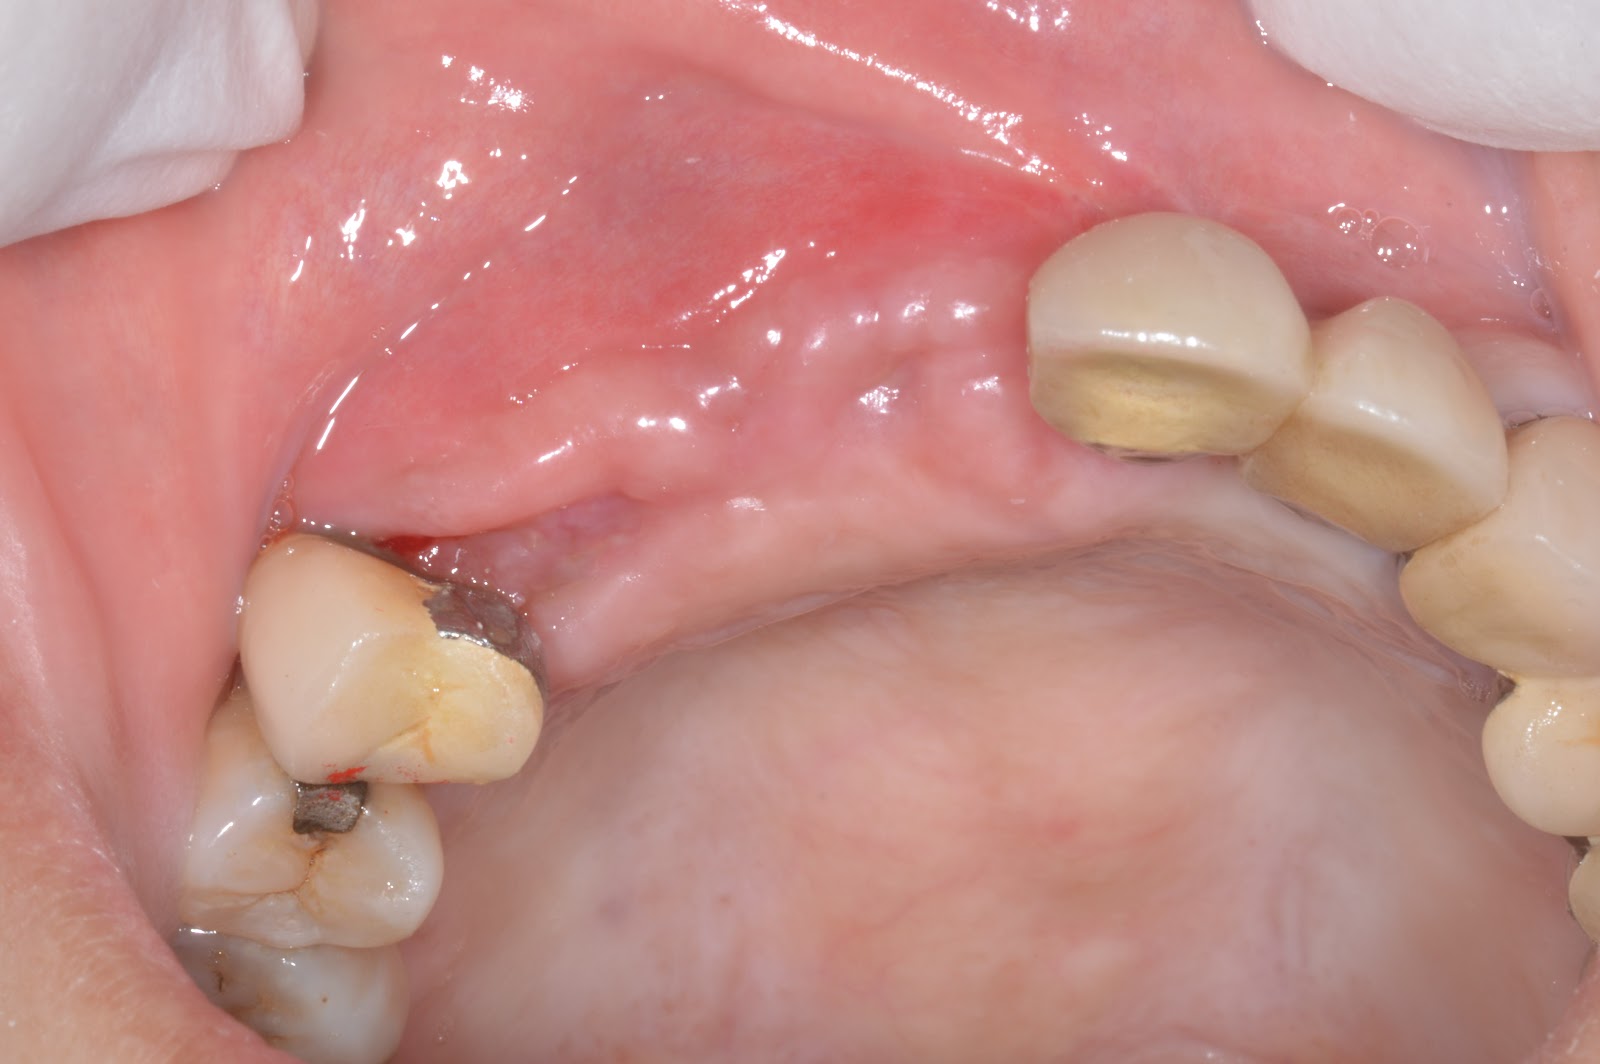

Pre-extraction